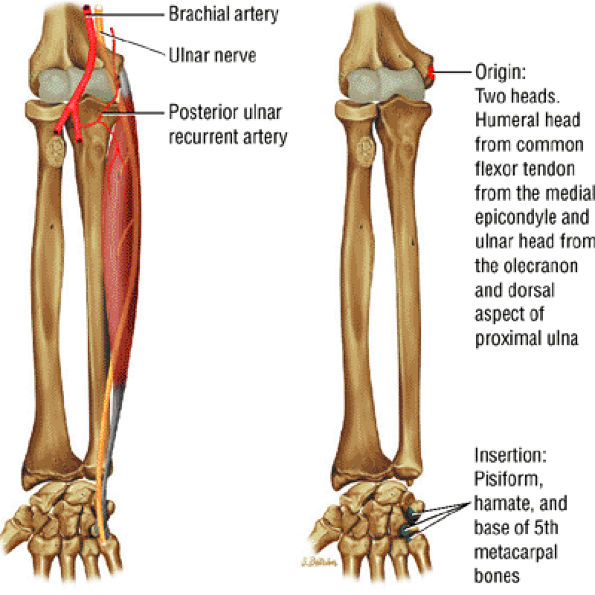

FIGURE 10.6 ● FLEXOR CARPI ULNARIS The flexor carpi ulnaris flexes and adducts the hand. It is an important dynamic stabilizer of the pisotriquetral joint and contributes superficial fibers to the pisohamate ligament. Since it lies superficial and just medial to the ulnar nerve, it serves as a marker when ulnar nerve block is performed.